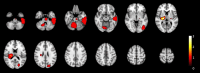

Methods: Using a simulation approach, we analyzed magnetic resonance imaging (MRI) scans of stroke-suspected patients within 4.5 h of symptom onset to assess TCCS and NIRS for identifying imaging-based IVT contraindications. Our study included both primary and sensitivity analyses, each employing conservative and optimistic scenarios. The primary analysis integrated clinical information from the emergency department, while the sensitivity analysis evaluated overall performance across all patients, regardless of clinical information. The conservative scenario defined TCCS detecting acute deep-brain hemorrhages or tumors >20 mm from scalp surface or > 10 mL in volume or causing >4 mm midline-shift, while NIRS was defined detecting them <20 mm from scalp surface with a volume > 3.5 mL. The optimistic scenario defined TCCS detecting intracranial or subarachnoid acute/subacute hematoma or tumors >20 mm from scalp surface or > 5 mL in volume or causing >2 mm midline-shift, while NIRS was defined detecting them <35 mm from the scalp surface with volume > 3.5 mL.

Results: We assessed 1,089 consecutive patients undergoing acute MRI, identifying 69 with imaging-based IVT contraindications, of which 40 had additional non-imaging contraindications. In the primary analysis, among those 29 patients without non-imaging-based contraindications, TCCS/NIRS would have detected 15 of 25 ICH and 3 of 4 malignant tumors in the conservative scenario. In the optimistic scenario, 18 of 25 ICH and all malignant tumors would have been detected. In the sensitivity analyses, the conservative scenario would have detected 30 of 52 ICH and 8 of 17 malignant tumors, while the optimistic scenario would have identified 37 of 52 ICH and 12 of 17 malignant tumors.